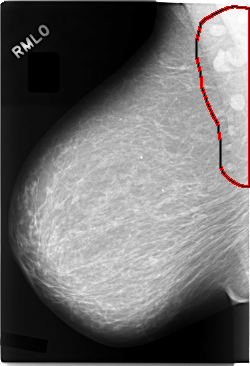

C_0083_1.RIGHT_MLO

RIGHT_MLO LINES 5848 PIXELS_PER_LINE 4000 BITS_PER_PIXEL 12 RESOLUTION 50 OVERLAY

FILE: C_0083_1.RIGHT_MLO.OVERLAY

TOTAL_ABNORMALITIES 1

ABNORMALITY 1

LESION_TYPE MASS SHAPE OVAL MARGINS CIRCUMSCRIBED

ASSESSMENT 5

SUBTLETY 5

PATHOLOGY MALIGNANT

TOTAL_OUTLINES 1

BOUNDARY